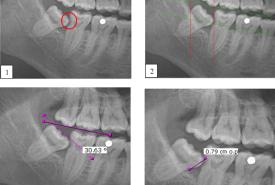

The Incidence of Mandibular Second Molar Distal Caries Associated with Impacted Mandibular Third Molar: A Retrospective Study and Management Guidelines

Original Article 21 Jul, 2025

Farah Hanan Fathihah Jaffar

• Read more about Farah Hanan Fathihah Jaffar

Khairul Osman

• Read more about Khairul Osman